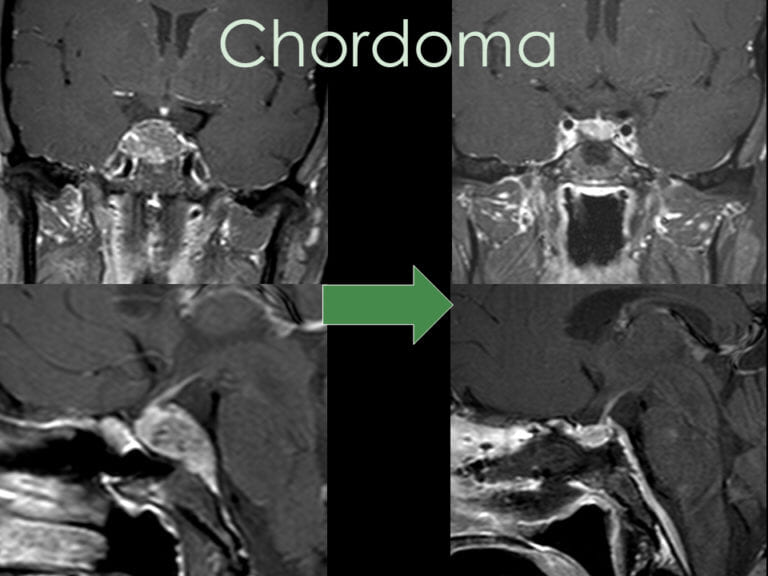

How is Chordoma Diagnosed?

Chordomas are initially identified through imaging studies, most commonly:

- CT scans, often ordered for sinonasal symptoms

- MRI with IV gadolinium contrast, using thin cuts through the clivus (often called a pituitary protocol)

The gold standard for chordoma treatment is surgical resection of the tumor. Most skull base chordomas are midline tumors and are best approached through a minimally invasive approach such as an endoscopic endonasal transclival approach through the nostrils.

Tumors with lateral extension may require alternative or combined approaches, such as a retrosigmoid craniotomy from behind the ear. The goal is maximal safe resection, prioritizing preservation of neurological function over aggressive removal.

Radiation Therapy

If residual tumor remains or regrowth occurs, additional treatment may include:

- Stereotactic radiosurgery

- Proton beam radiation

- Or a combination of both

These therapies provide approximately 80% tumor control, with proton therapy offering advantages in select cases depending on tumor location.